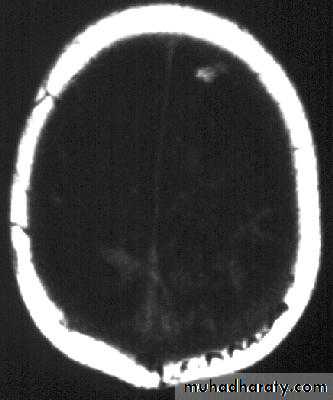

Bacterial Meningitis with cerebral oedema